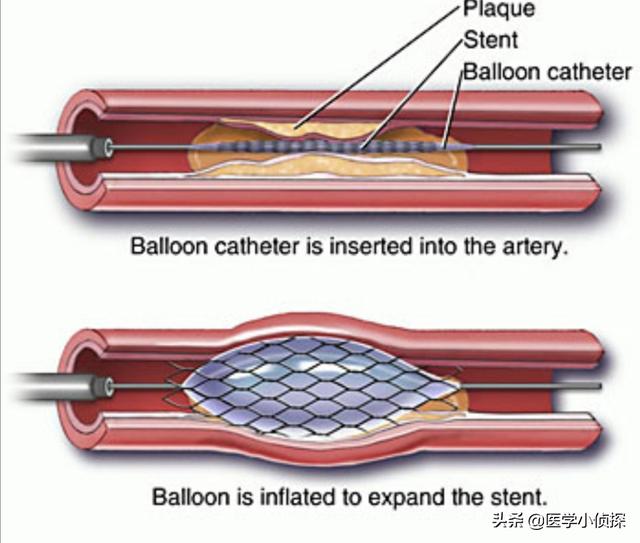

ステップ3:軌道を確立する。最初のガイドワイヤーは冠動脈より太いので、この時は細いガイドワイヤーを選んで冠動脈病変の遠位部を通過させ、まずバルーンで拡張しなければならない。

ステップ4:ステントを留置する。バルーンの拡張が完了したら、このガイドワイヤーに従ってステントを留置する。

これが心臓ステント手術の大まかな流れだ。 経験を積んだ。熟練した医師は、この手術を30分以上かけて行う!そのため、心臓ステント手術を専門とする医師にとっては、そうである。大きな作戦ではない。。